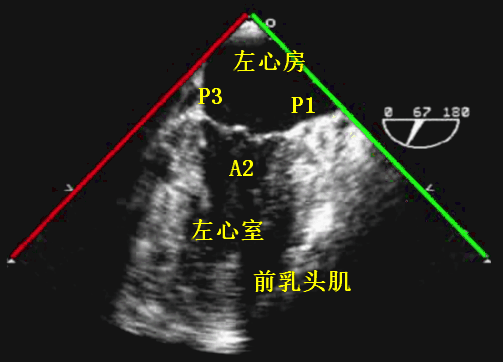

超声解剖刀的「切割方向」角度是根据后前位(即从后往前看)作为参考平面。以食管中段切面为例,0° 时的扫描切面即 TEE 探头的水平切面(横轴切面);30°~50° 时的扫描切面相当于心脏的短轴切面;90° 时的扫描切面相当于 TEE 探头的矢状切面;110°~130° 时的扫描切面相当于心脏的长轴切面;180° 时的扫描切面为 0° 时所得切面的镜像图。

探头从 0°~180° 连续旋转晶片,理论上可获得无数个连续性的诊断切面。

图 6:超声切面角度示意图(后前位、食管中段切面)